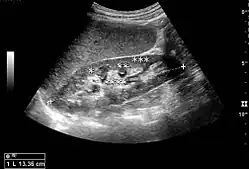

Cystic renal masses

Masses are seen as a distortion of the normal renal architecture. Most renal masses are simple cortical renal cysts with a round appearance and a smooth thin capsule encompassing anechoic fluid. The incidence increases with age, as at least 50% of people above the age of 50 have a simple cyst in one of the kidneys. Cysts cause posterior enhancement as a consequence of reduced attenuation of the ultrasound within the cyst fluid (Figure 5). The simple cyst is a benign lesion, which does not require further evaluation.[1]

Figure 5. Simple renal cyst with posterior enhancement in an adult kidney. Measurement of kidney length on the US image is illustrated by '+' and a dashed line.[1] -